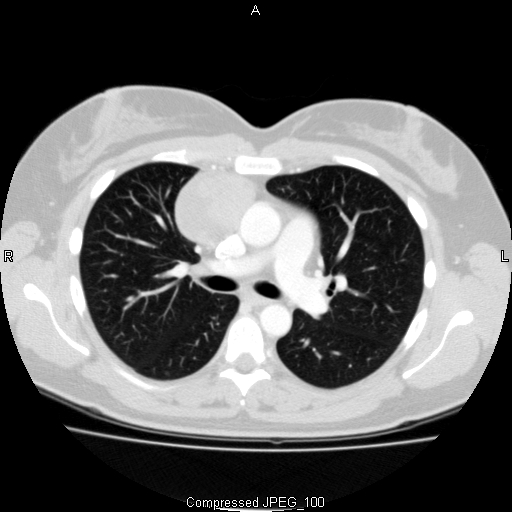

Although rare, thymomas are the most frequently occurring tumors of the anterior mediastinum. They account for approximately 35-50% of all anterior mediastinal masses (1, 3). Other commonly occurring tumors of the anterior mediastinum include lymphoma (25%), thyroid and parathyroid tumors (15%), benign teratoma (10%), malignant germ cell tumors (10%), and benign thymic lesions (5%) (4). It is essential to differentiate thymic malignancies from other anterior mediastinal masses prior to treatment. Evaluation of an anterior mediastinal mass should begin with a detailed history and physical. Age and gender are particularly important, as specific lesions tend to occur more frequently in certain demographic groups. The presence of local or systemic symptoms may also help differentiate the type of lesion. CT imaging is the preferred imaging modality, as the appearance of a mass may be highly suggestive of a particular diagnosis (Figure 1). MRI can be helpful in distinguishing solid and cystic lesions. CT-PET is not recommended for the routine evaluation of a thymoma, but is useful in staging lymphoma and evaluating response to therapy. Laboratory studies are an important adjunct as well. Elevated levels of α-fetoprotein (α-FP) and β-human chorionic gonadotropin (β-HCG) are diagnostic of non-seminomatous germ cell tumors, while elevated lactate dehydrogenase (LDH) is a common finding in lymphoma (4).

Figure 1: CT image demonstrating a well-encapsulated

anterior mediastinal mass representative of an early stage

thymoma.